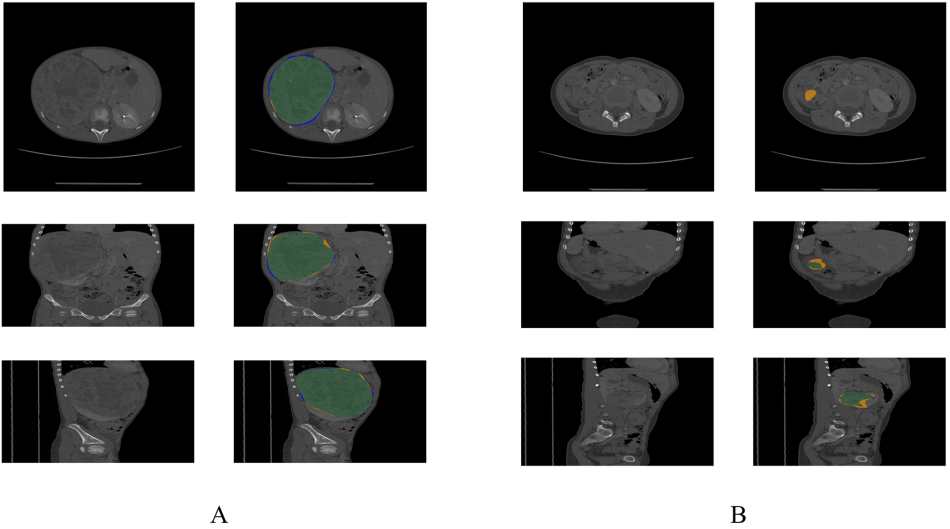

A: CT image of a patient with DSC of 0.9715

B: CT image of a patient with DSC of 0.2927

green area: manual segmentation & automatic segmentation 겹치는 부분

blue area: manual segmentation

yellow area: automatic segmentation